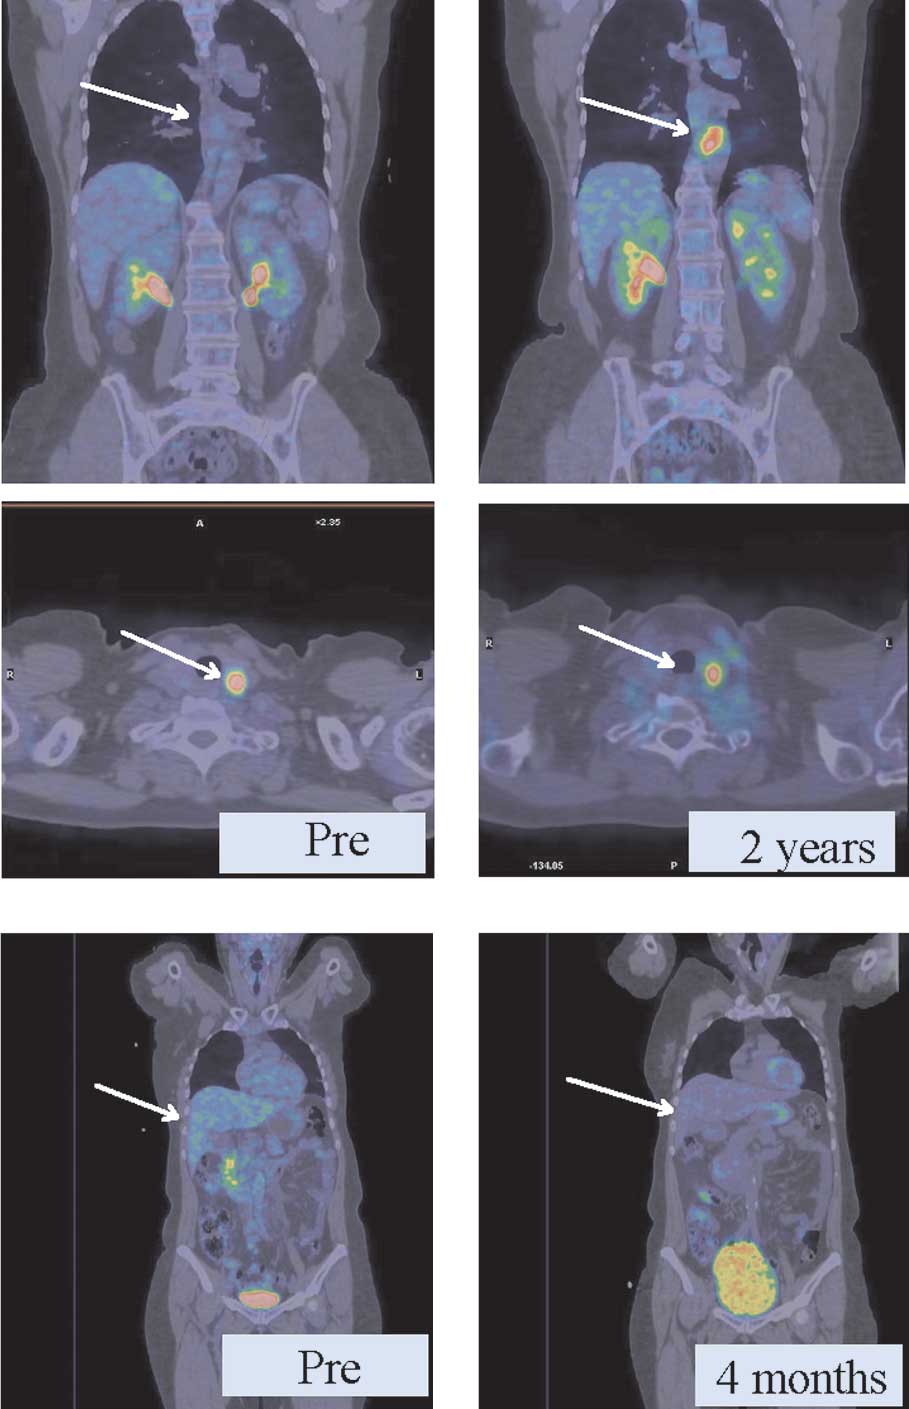

PET-CT imaging

We used PET-CT to evaluate both groups and observed that in the group with bDLE as adjuvant the regression of metastatic lesions in diverse anatomic locations was obtained in less time than in the control group (without bDLE). As shown in Fig. 4A, patients with metastatic breast cancer without adjuvant therapy had persistent thyroid lesions and a new lesion around the aorta (2 cm) after 2 years of chemotherapy. In another case (Fig. 4B), retroperitoneal retrohepatic metastases exhibited a PR, with the same metabolic activity (6 SUV) after only 4 months of receiving bDLE treatment and 5 cycles of chemotherapy.

Figure 4.

Clinical effect of bDLE as visible in PET images. In the control group, we observed no response (A) of thyroid lesions after chemotherapy without bDLE. (B) Partial regression of retroperitoneal retrohepatic metastases after chemotherapy and bDLE treatment. Pre-, pre-treatment.